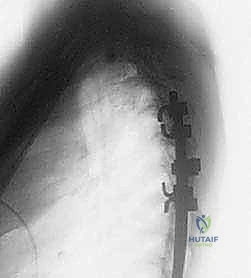

عملية دمج الفقرات (Spinal Fusion) هي إجراء جراحي يهدف إلى ربط فقرتين أو أكثر بشكل دائم، مما يزيل الحركة غير الطبيعية والمؤلمة بينهما، ويعيد الاستقرار الميكانيكي إلى العمود الفقري. في حالتنا هذه، يتم التركيز بشكل خاص على المنطقة الصدرية القطنية (Thoracolumbar Junction)، وهي المنطقة الانتقالية الحرجة التي تربط الجزء العلوي من الظهر (القفص الصدري الصلب) بالجزء السفلي (المنطقة القطنية المتحركة). يتم التثبيت باستخدام أدوات طبية معدنية متطورة (Instrumentation) مثل المسامير السويقية (Pedicle Screws) والقضبان المصنوعة من التيتانيوم.

* الأشعة السينية (X-rays): خاصة الصور الديناميكية (أثناء الانحناء للأمام والخلف) لتقييم درجة عدم الاستقرار الميكانيكي والانزلاق.

* التصوير المقطعي المحوسب (CT Scan): يوفر صوراً ثلاثية الأبعاد للعظام، وهو ضروري جداً للتخطيط الجراحي الدقيق وتحديد أحجام المسامير المناسبة لكل سويقة فقارية.